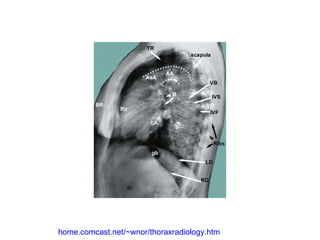

home.comcast.net/~wnor/thoraxradiology.htm